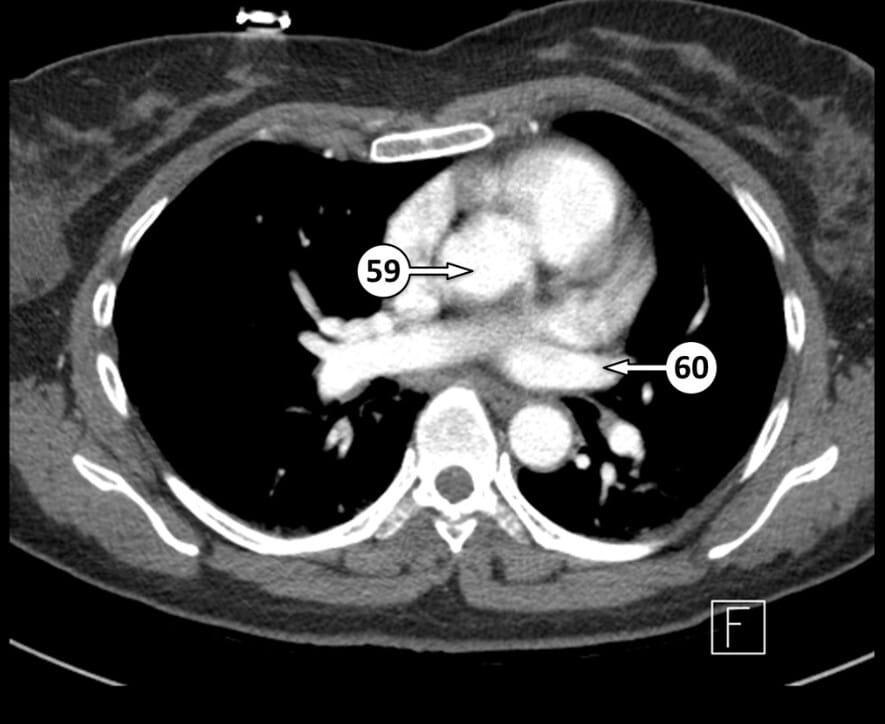

59.ascending aorta

60. left superior pulmonary vein